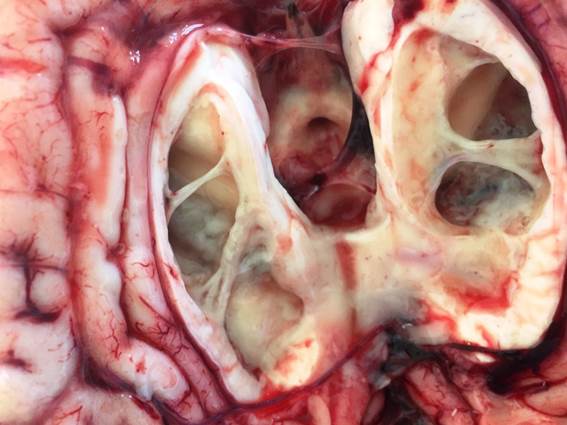

Todos los casos se caracterizaron por un cuadro clínico nervioso de ataxia, temblores, pedaleo, convulsiones, decúbito costal y muerte en 12 horas. Las lesiones macroscópicas predominantes se localizaban en el encéfalo y correspondían a la forma patológica conocida como Leptomeningitis / Ventriculitis/ Coroiditis. El encéfalo en todos los casos estaba congestivo y edematoso, con las meninges engrosadas y abundante contenido de pus y fibrina en el interior de los ventrículos laterales.

Figura 1: Sistema Nervioso Central (caso Nº 4). Ventriculitis. Contenido fibrino-purulento en ambos ventrículos laterales.

No se encontraron focos necróticos-hemorrágicos típicos de TEM. En un animal ( caso Nº 4 ) se observó una severa pericarditis fibrino supurativa.